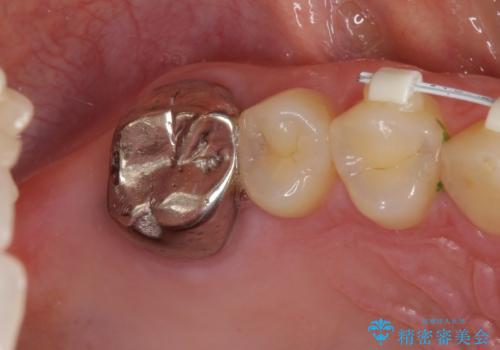

- 前歯の隙間と奥歯の目立つ銀歯を気にして来院された患者様です。

インビザラインにより下顎前歯の隙間を閉じるとともに、奥歯の咬み合わせを改善させることとしました。

矯正治療後には、銀歯のクラウンをセラミッククラウンへ替える補綴治療を行うこととしました。